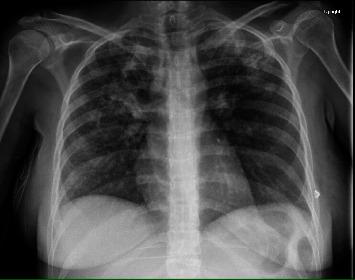

Peritoneal tuberculosis is a rare form of extrapulmonary tuberculosis and presents a challenging diagnosis because of its nonspecific clinical manifestations. Peritoneal TB mimics other pathologies, including abdominal carcinomatosis, especially when the patient presents with ascites and an elevated cancer antigen (CA)-125 levels. . A postpartum 20-year-old Hispanic female recently discharged after transverse cesarean surgery, presented to the ER with fever, chills, edema, abdominal distension, nausea, and vomiting. The patient was febrile, tachycardic, and hypotensive. Chest X-ray demonstrated alveolar and interstitial consolidations; chest CT revealed tree-in-bud opacities in the right lower lobe, suggestive of atypical (TB)/fungal infection. CT of the abdomen and pelvis demonstrated ascites, omental thickening, peritoneal thickening, and mesenteric adenopathy, suggestive of carcinomatosis. She was admitted with a presumed diagnosis of sepsis secondary to pneumonia and started empirically on broad-spectrum antibiotics without clinical improvement. A battery of oncology markers was ordered and revealed a mildly elevated cancer antigen (CA)-125. Diagnostic paracentesis showed lymphocytic predominance with positive mycobacteria PCR, elevated adenosine deaminase (ADA), and no malignant cells. Subsequently, the sputum acid-fast bacilli (AFB) stain returned positive for tuberculosis, confirming the diagnosis of pulmonary tuberculosis. A peritoneal biopsy was obtained and demonstrated caseating granulomas consistent with peritoneal tuberculosis. The patient was started on standard antituberculosis therapy with clinical improvement.

腹膜结核是肺外结核的一种罕见形式,因其临床表现不具特异性,诊断颇具挑战性。腹膜结核可模仿其他病症,包括腹部癌转移,尤其是当患者出现腹水且癌抗原(CA)-125水平升高时。一名20岁的西班牙裔产后女性,在接受横切剖宫产手术后近期出院,因发热、寒战、水肿、腹胀、恶心和呕吐前往急诊室就诊。患者发热、心动过速且血压降低。胸部X光显示肺泡和间质实变;胸部CT显示右下叶有树芽征,提示非典型(结核)/真菌感染。腹部和盆腔CT显示有腹水、网膜增厚、腹膜增厚和肠系膜淋巴结肿大,提示癌转移。她因疑似肺炎继发败血症入院,并经验性地开始使用广谱抗生素,但临床症状无改善。一系列肿瘤标志物检查显示癌抗原(CA)-125轻度升高。诊断性腹腔穿刺显示以淋巴细胞为主,结核分枝杆菌聚合酶链反应阳性,腺苷脱氨酶(ADA)升高,且无恶性细胞。随后,痰抗酸杆菌(AFB)染色结核呈阳性,确诊为肺结核。进行了腹膜活检,结果显示有干酪样肉芽肿,符合腹膜结核。患者开始接受标准抗结核治疗,临床症状有所改善。